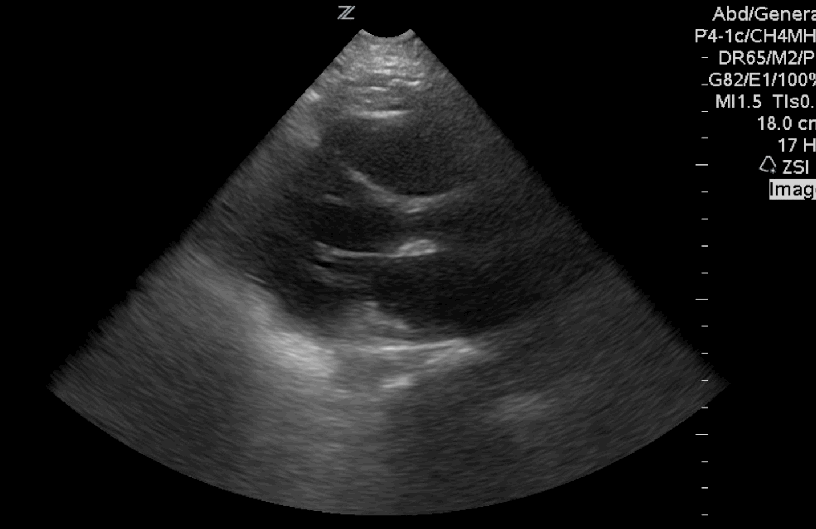

#FOAMus #FOAMcc and #disco all in one for this #Sono of the Week #POCUS in V Fib